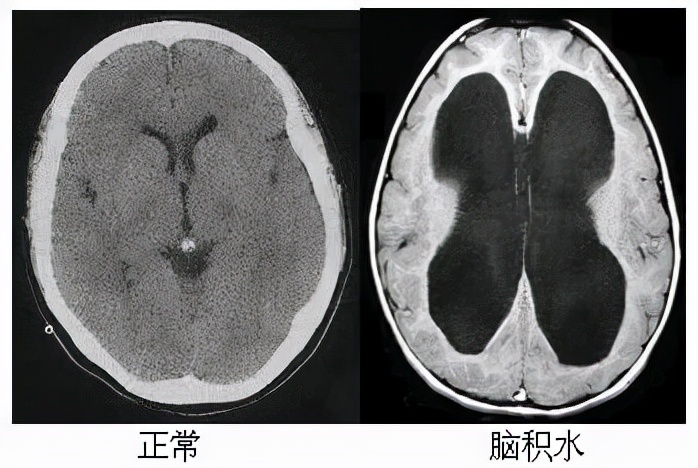

首先我们来个感性认识!上图看真相:

上图脑积水的影像图显示双侧侧脑室明显扩大(中间大大的黑蝴蝶)。如果我们看到这样的影像片子,一定要想到“脑积水”这个术语。